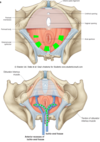

What are the Internal Pudendal Artery Branches?

- Inferior rectal artery (Anal canal & sphincters)

- Perineal artery

- branches to Posterior scrotal or labial arteries.

• Terminal branches

- Artery to the bulb of the penis or vestibule

- Deep artery of the penis or clitoris

- Dorsal artery of the penis or clitoris

Which artery is essential for erection?

Deep artery of the penis!

* The deep artery of the penis or clitoris each enters a crus (corpora cavernosa).

What are the Internal Pudendal Vein tributaries?

- Inferior rectal vein

- Posterior scrotal or labial vein

- Vein to the bulb of the penis or vestibule

What are the exceptions to the tributaries of the Internal Pudendal Vein (meaning the veins that dont feed into the internal pudendal vein)?

- Deep dorsal vein of penis or clitoris: drains glans & corpora cavernosa; drains in prostatic plexus (male) or vesical plexus (female) of veins.

- Superficial dorsal vein of the penis or clitoris: drains corpus spongiosum, urethra, fascia & skin of penis in external pudendal vein (femoral vein)

Lymph Drainage from the Perineum is mainly to the superficial and deep inguinal lymph nodes, with important exceptions:

- The testis drains to lateral aortic nodes in the abdomen.

- Some lymph vessels follow the round ligament of the uterus from the uterus to the labium majus, which then drains to superficial inguinal nodes.

The Ischio anal fossa is filled with fat & loose connective tissue. It is bordered by skin, gluteus maximus, obturator internus and fascia, levator ani and fascia, and external anal sphincter.

On the lateral wall is the…………… containing the…………….

Pudendal canal

pudendal nerve & vessels

Crossing the ischioanal fossa are the…………………..

inferior rectal nerves and vessels (branch from pudendal n. and internal pudendal a. and v. at the sciatic notch)

What is important to note clinically about the Ischioanal fossae?

It is a common site for abscess formation. An infection in one ischioanal fossa may spread behind the anal canal into the other ischioanal fossa.

The anal canal is surrounded by what 3 things?

- Internal anal sphincter (smooth muscle)

- External anal sphincter (skeletal muscle)

- Fat of the ischioanal fossa